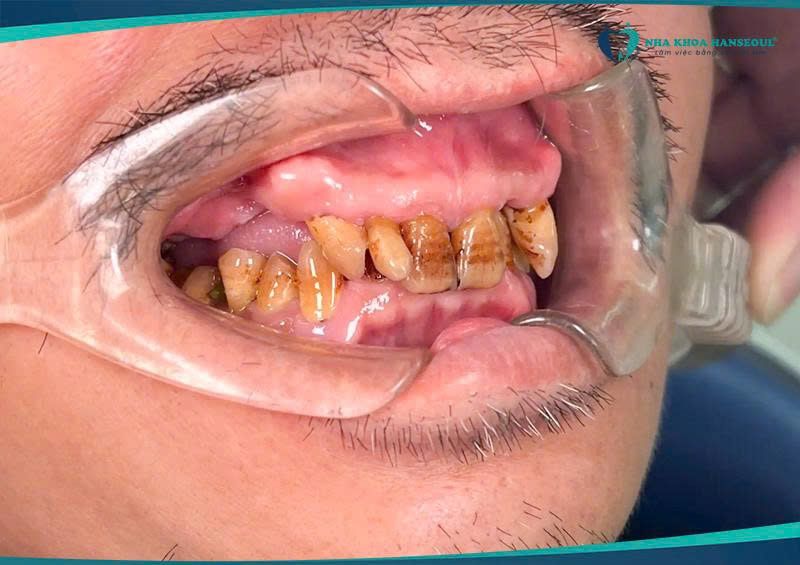

Suốt nhiều năm, chú Khổng Doãn Tuấn Ngọc sống chung với tình trạng mất nhiều răng hàm — từ 17, 16, 14 ở hàm trên đến 35, 36, 37 ở hàm dưới. Việc ăn uống ngày càng trở nên bất tiện; nhai không kỹ, ăn đồ cứng thì đau, thậm chí có lúc chú phải chọn món “an toàn” hơn chứ không còn thoải mái như trước. Điều khiến chú ngại nhất chính là nỗi sợ đau và cảm giác “làm răng chắc vất vả lắm” — và vì thế chú cứ chần chừ mãi.

Đến khi thấy việc ăn uống ảnh hưởng quá nhiều đến sinh hoạt hằng ngày, chú quyết định tìm đến Nha khoa Hanseoul để kiểm tra và tư vấn bác sĩ. Kết quả thăm khám cho thấy xương ở một số vị trí đã tiêu nhiều do mất răng lâu, đặc biệt ba răng hàm trên (14 – 16 – 17) cần ghép bột xương và đặt màng xương để tái tạo nền vững. Phác đồ điều trị được thạc sĩ, bác sĩ Trần Việt Hà đưa ra gồm: cấy 5 trụ implant và phục hình 6 răng (bắc cầu răng 36 trên trụ răng 35 và 37) — kế hoạch rõ ràng, bài bản và phù hợp nhất để chú có thể ăn uống bình thường trở lại.